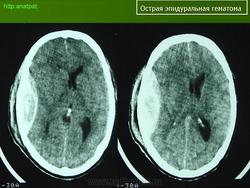

2. КТ головного мозга, демонстрирующее редкий случай эпидуральной гематомы снования черепа (указано стрелкой)